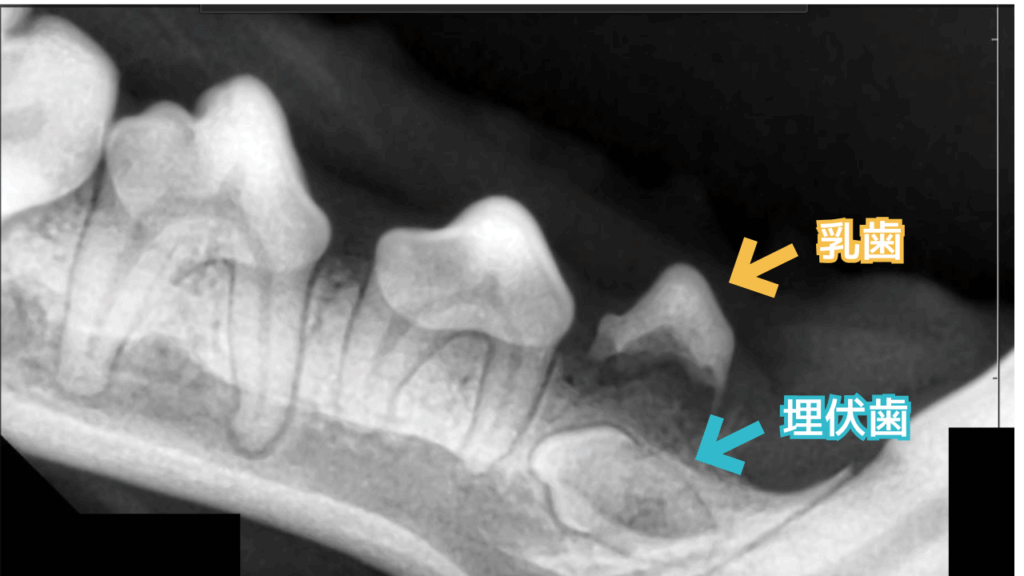

このタイミングで**歯科レントゲン(デンタルX線)**を撮ることで、

目に見えない「歯根の吸収不全」「埋伏歯」「永久歯の萌出異常」を早期に発見できます。

🔎歯科レントゲンで分かること

- 残根や埋伏歯の有無

- 永久歯の向きや位置

- 乳歯の根吸収の程度

- 骨との位置関係

これにより、将来的な咬合異常や歯周病のリスクを大幅に減らすことができます。

埋伏歯など歯の異常を認めた場合は麻酔下での治療が必要になります。